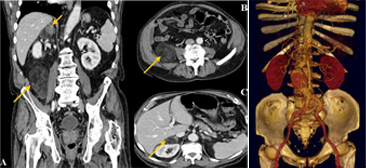

복부 단층 촬영

간, 위, 신장, 췌장, 비장, 담낭, 십이지장, 자궁, 방광, 소장, 대장 등 복부 장기의 질병을 검사합니다.